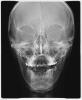

Skip Опубликовано 3 августа, 2012 Поделиться Опубликовано 3 августа, 2012 Здравствуйте, Юля. Вариант с удалением 4-ки мне не нравится. Не нравится по нескольким причинам, а в частности меня интересует механика, с помощью которой будет проводится последующая ретракция передних зубов. Там будет необходим абсолютный анкораж, а у меня есть большие сомнения в том, что для этого будут использоваться минивинты, учитывая что проходите лечение в муниципальной полуклинике. Я всегда оказываюсь в крайне для себя затруднительном положении, когда ко мне приходят пациенты на этапе уже проводимого лечения. Тем более такого лечения, когда даже не был поставлен диагноз (читайте между строк). Вы же сами теперь убедились, что необходимо было сделать прежде, чем инсталлировать брекет-систему, не говоря уже, о принятии решения удаления отдельных зубов. Но, 8-ки вверху удалять однозначно и делать это нужно не по окончании лечения, а уже сейчас.. Внизу тоже, но какую точно, нужно смотреть, возможно обе. Но опять же, речь сейчас не должна вестись вокруг отдельных зубов, это дело техники (тактика ортодонта). Речь о том, как Ваш лечащий врач видит стратегию (логика ортодонта) лечения:1) Патологии прикуса Класс II-I, высокий угол с тенденцией к открытому прикусу.2) Вправляемого вывиха диска. http://s015.radikal.ru/i333/1208/ae/7419e042feaf.jpg Интересно, почему Ваш доктор решил удалять 8-ки в конце лечения? Сейчас с увернностью могу сказать, что он понятия не имеет об окклюзионной плоскости и как работать с этой плоскостью при патологии Класса II/открытый прикус. Иначе, это удаление было бы перед началом лечения и ставило бы определённую задачу. Сейчас нужно заниматься положением языка и установлением правильного типа глотания, т.к. это предопределит положение шейного отдела позвоночника, головы, нижней челюсти, суставов, а также функции дыхания. Удаление 4-ки на верхней челюсти и последующая ретракция фронта окажет крайне негативное влияние на вышеперечисленное, так верхняя челюсть находится в ретропозиции. Положение языка, при данной патологии, является критическим. Это также будет оказывать влияние и на ретенции полученных результатов.Симметрии центра, после удаления верхней 4-ки, тоже врядли добьётесь. Кстати, сходите к ЛОРу, пусть дадут своё заключение. Что доктор собирается проводить на нижнем зубном ряду? Как будет проводиться апрайтинг и дистализация 7-ок без удаления 8-ых? Или также, как на верхней, прицепят дугу и будут ждать чуда от дядюшки Даймон? Ссылка на комментарий

Andrey Senyuk Опубликовано 15 августа, 2012 Поделиться Опубликовано 15 августа, 2012 Я извиняюсь, посмотрела в карту на 18 записана. как лучше быть-то. Я сейчас в области проживаю, к местным врачу (лору) идти бессмысленно. Ну а может такой вариант: поставлю на нижнюю, потом к вам подъеду. Или на НЧ в данном случае лучше пока не ставить, пока к вам не попаду. И как быть с ВЧ, менять ли дугу.Лечение свет)А что там у Вас в орбитах (глазах) Ссылка на комментарий

Force Опубликовано 15 августа, 2012 Поделиться Опубликовано 15 августа, 2012 это ближе к носу... Ссылка на комментарий

kostu4ok Опубликовано 20 августа, 2012 Автор Поделиться Опубликовано 20 августа, 2012 это вы про точки, расположенные возле носа, я даже не представляю что это такое. В вашей практике такого не видели? Сэтим надо к лору обращаться или куда? Ссылка на комментарий